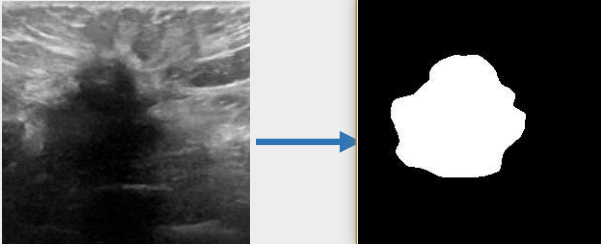

## 算法原理 U-KAN与其它图像分割算法一样,将图片数据送入模型后,依次通过预处理、特征提取,最后经过卷积预测出像素类别实现分割。

## 环境配置 ``` mv U-KAN-optimize_pytorch U-KAN # 去框架名后缀 # if torch>2.0, modify /usr/local/lib/python3.10/site-packages/timm/models/layers/helpers.py: from torch._six import container_abcs -> import collections.abc as container_abcs ``` ### Docker(方法一) ``` docker pull image.sourcefind.cn:5000/dcu/admin/base/pytorch:2.1.0-ubuntu20.04-dtk24.04.1-py3.10 # 为以上拉取的docker的镜像ID替换,本镜像为:a4dd5be0ca23 docker run -it --shm-size=32G -v $PWD/U-KAN:/home/U-KAN -v /opt/hyhal:/opt/hyhal:ro --privileged=true --device=/dev/kfd --device=/dev/dri/ --group-add video --name ukan bash cd /home/U-KAN pip install -r Seg_UKAN/requirements.txt # requirements.txt ``` ### Dockerfile(方法二) ``` cd U-KAN/docker docker build --no-cache -t ukan:latest . docker run --shm-size=32G --name ukan -v /opt/hyhal:/opt/hyhal:ro --privileged=true --device=/dev/kfd --device=/dev/dri/ --group-add video -v $PWD/../../U-KAN:/home/U-KAN -it ukan bash # 若遇到Dockerfile启动的方式安装环境需要长时间等待,可注释掉里面的pip安装,启动容器后再安装python库:pip install -r Seg_UKAN/requirements.txt。 ``` ### Anaconda(方法三) 1、关于本项目DCU显卡所需的特殊深度学习库可从光合开发者社区下载安装: - https://developer.hpccube.com/tool/ ``` DTK驱动:dtk24.04.1 python:python3.10 torch:2.1.0 torchvision:0.16.0 ``` `Tips:以上dtk驱动、python、torch等DCU相关工具版本需要严格一一对应。` 2、其它非特殊库参照requirements.txt安装 ``` pip install -r Seg_UKAN/requirements.txt # requirements.txt ``` ## 数据集 `BUSI(Breast Ultrasound Image)` - https://www.kaggle.com/datasets/aryashah2k/breast-ultrasound-images-dataset 本项目无需下载原始数据集,采用U-KAN作者提供的预处理数据[pre-processed dataset](https://mycuhk-my.sharepoint.com/:f:/g/personal/1155206760_link_cuhk_edu_hk/ErDlT-t0WoBNlKhBlbYfReYB-iviSCmkNRb1GqZ90oYjJA?e=hrPNWD) 即可。 项目中已包含[`busi`](./Seg_UKAN/inputs/busi.zip),解压即可使用,训练数据目录结构如下: ``` Seg_UKAN ├── inputs │ ├── busi │ ├── images │ ├── malignant (1).png | ├── ... | ├── masks │ ├── 0 │ ├── malignant (1)_mask.png | ├── ... ``` 数据集快速下载中心:SCNet AIDatasets ,项目中预处理数据集可从快速下载通道下载:[busi_cvc_glas_preprocessed](http://113.200.138.88:18080/aidatasets/project-dependency/busi_cvc_glas_preprocessed.git) 。 ## 训练 ### 单机单卡 ``` # 以公开数据集busi为基础进行算法效果优化 cd Seg_UKAN python train.py --arch UKAN --dataset busi --input_w 256 --input_h 256 --name busi_UKAN --data_dir ./inputs ``` 更多资料可参考源项目的[`README_origin`](./README_origin.md) ## result

### 精度 数据集:busi,max epoch为400,训练框架:pytorch。 | 算法 | Dice | |:---------:|:------:| | U-KAN | 78.75% | | U-KAN-optimize | 79.64% | ## 应用场景 ### 算法类别 `图像分割` ### 热点应用行业 `医疗,电商,制造,能源` ## 源码仓库及问题反馈 - http://developer.hpccube.com/codes/modelzoo/u-kan-optimize_pytorch.git ## 参考资料 - https://github.com/CUHK-AIM-Group/U-KAN.git - https://github.com/KindXiaoming/pykan.git - https://kindxiaoming.github.io/pykan/